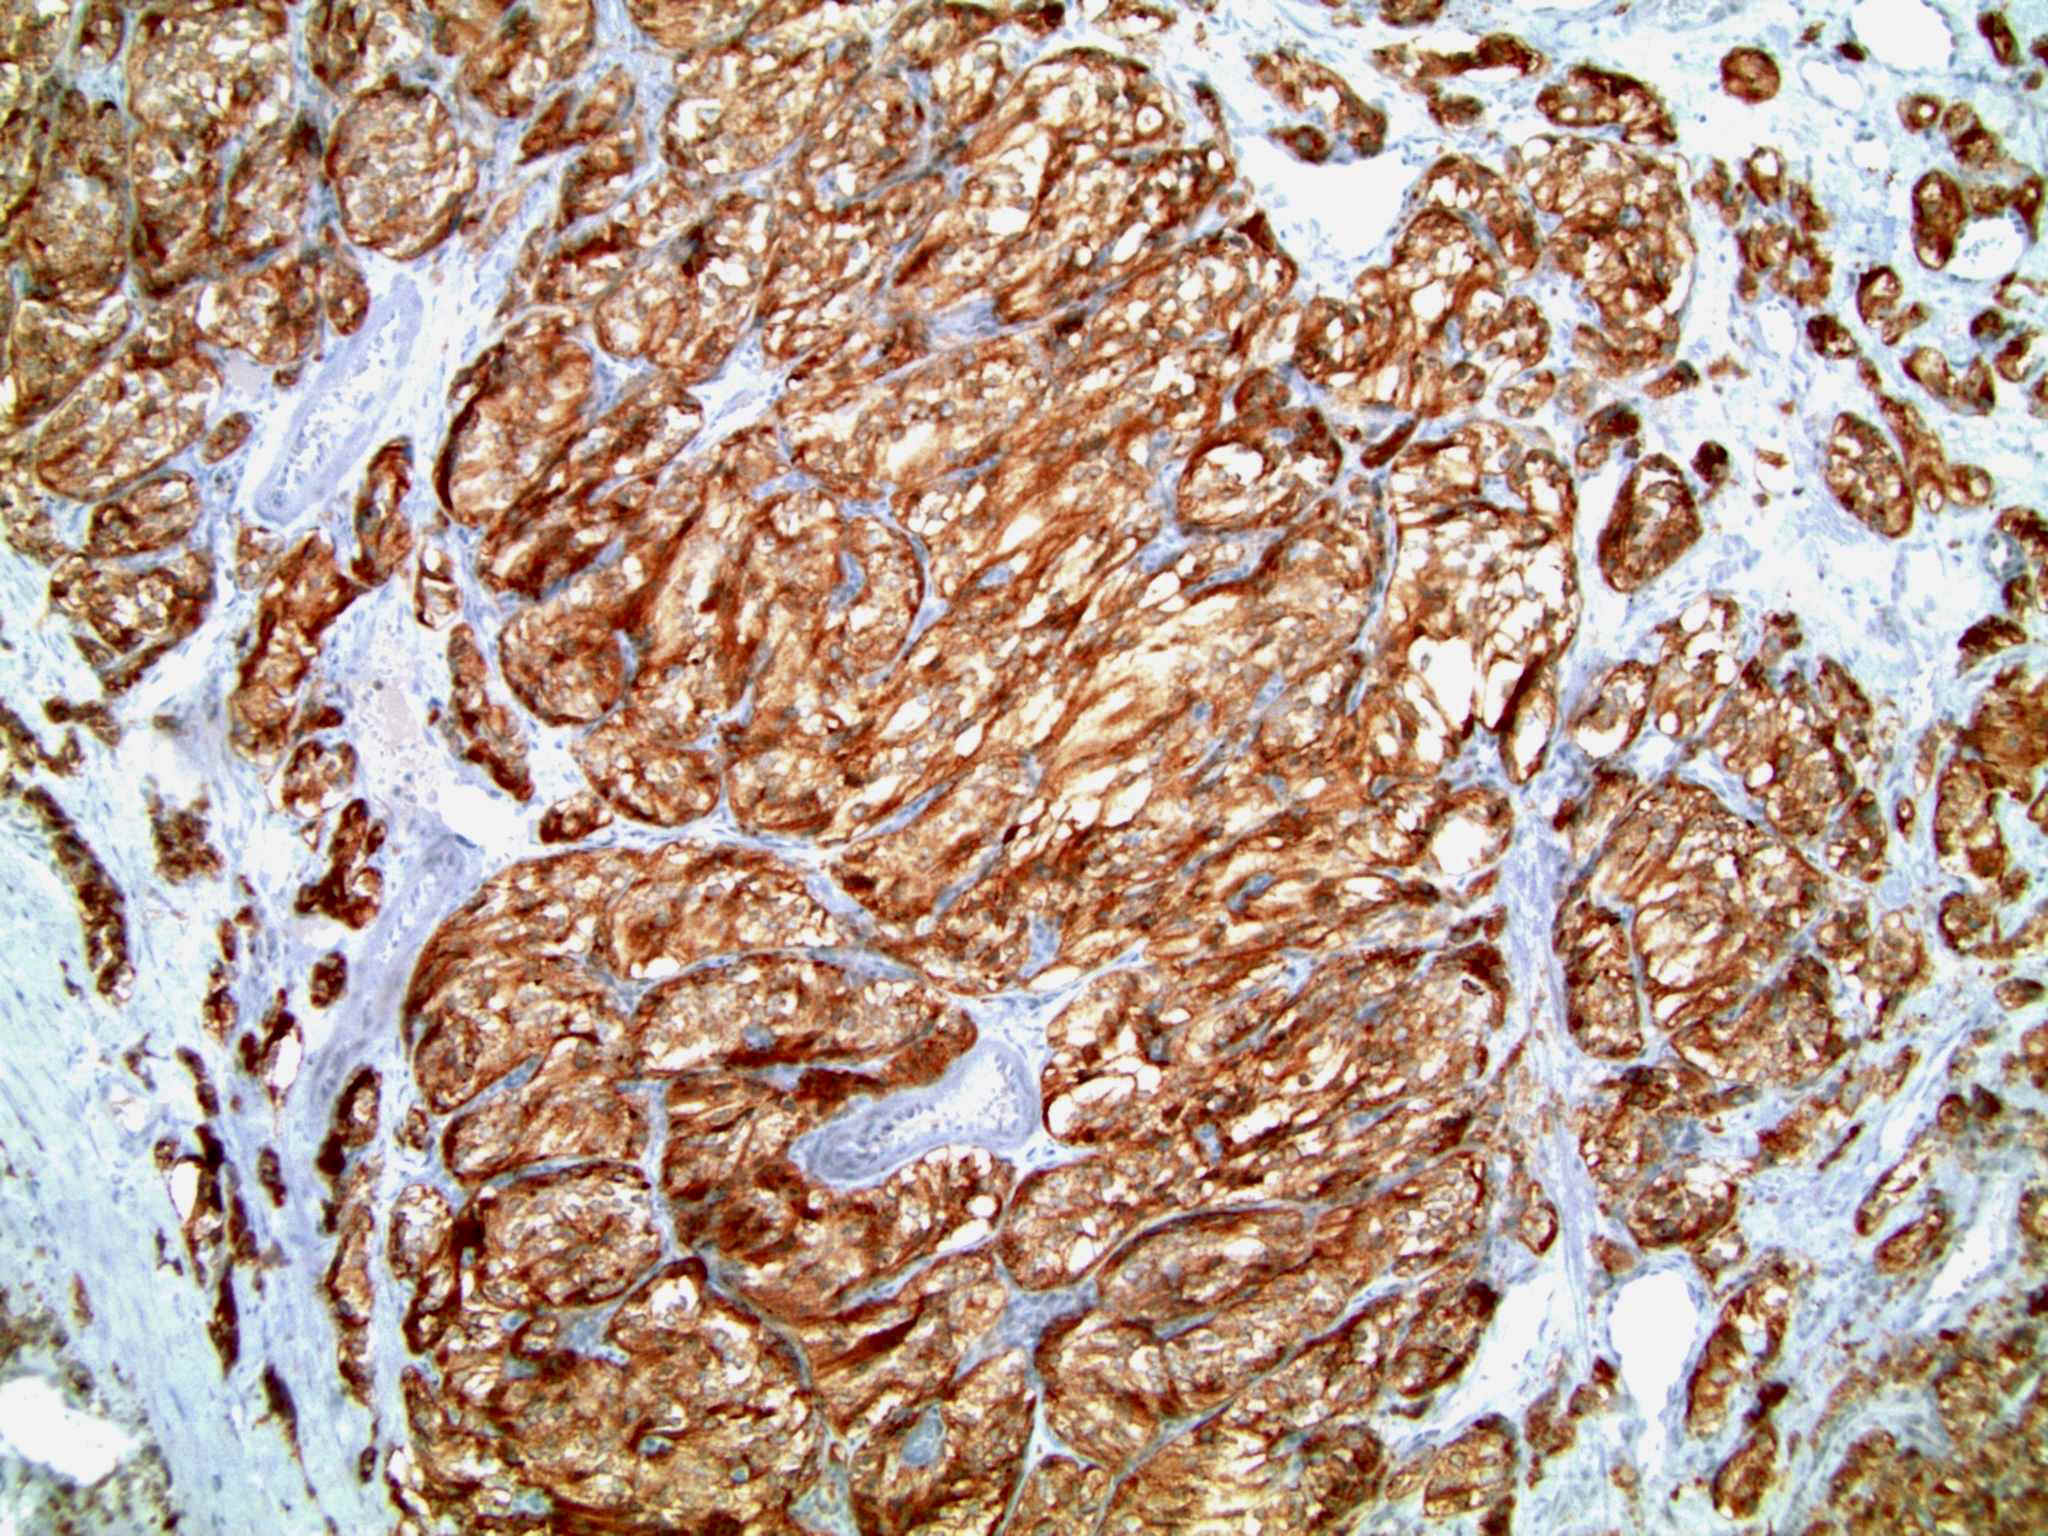

Microscopic (histologic) description

- Typical morphology: epithelioid cells with abundant, eosinophilic / amphophilic, granular cytoplasm and round / ovoid, vesicular / salt and pepper nuclei, arranged in a nested / zellballen pattern and separated by fibrovascular septae with sustentacular cells (Am J Surg Pathol 2004;28:94, World J Clin Cases 2014;2:591, Endocr Pathol 2022;33:90)

- May have focal pleomorphism, nuclear hyperchromasia, low mitotic activity or clear cytoplasm

Microscopic (histologic) images

Contributed by Theodorus H. van der Kwast, M.D., Ph.D., Michelle R. Downes, M.D., Debra L. Zynger, M.D. and David Cohen, M.B.B.Ch., M.D.

Positive stains

- INSM1 (diffuse), chromogranin A (variable, often diffuse), synaptophysin (variable, usually diffuse) (Endocr Pathol 2022;33:90)

- GATA3

- SSTR2 (Hum Pathol 2019:86:66)

- Sustentacular cells: S100, SOX10

- Microscopic description: This specimen shows an unencapsulated, monomorphous population of round tumor cells in a nested / zellballen pattern with delicate vascular septa and intervening extravasated red blood cells. It predominantly involves the lamina propria of the bladder but in 1 tissue piece clearly involves muscularis propria. The tumor cells have abundant amphophilic cytoplasm and vesicular chromatin with occasional small nucleoli. There is no necrosis, diffuse growth pattern or vascular space invasion identified. The mitotic count is (maximally) 1/10 high power fields. Immunohistochemistry shows the tumor cells to be positive for GATA3 with strong and diffuse expression of synaptophysin and chromogranin, as well as retention of SDHB staining. The tumor cells are negative for AE1 / AE3, HMWK and p63. The Ki67 proliferation index is < 1%. S100 shows faint nuclear and cytoplasmic staining with occasional sustentacular cells identified.